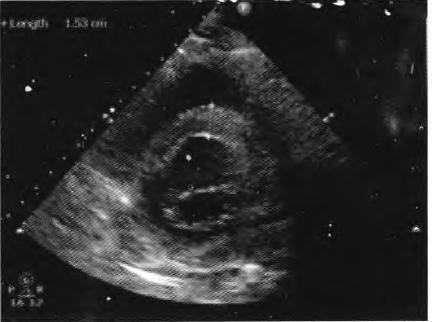

患者择期于10月25日行冠状动脉介入治疗,术前常规给予地塞米松10 mg静脉注射,右侧桡动脉穿刺成功后,经鞘管送多功能造影导管至主动脉窦部,对比剂选择碘帕醇(商品名:碘必乐),导管“吾烟”后数秒钟,患者血压骤然降低至50/30 mmHg,心率逐步增快至90次/min左右,予羟乙基淀粉130/0.4氯化钠注射液(万汶)加压快速静脉滴注100 mL,反复3次静脉注射多巴胺3 mg,血压65/40 mmHg左右,约3 min后心率降至40次/min左右,监护示室性逸搏心律,继之心跳、呼吸骤停。持续胸外按压,气管插管机械通气,持续静脉泵入肾上腺素0.2仙g/(kg•min),并间断4次静脉注射肾上腺素0.5 mg,血压维持在105/50 mmHg左右,进一步行左室造影,见图1。以及左冠状动脉造影,见图2。氧饱和度降至75%,考虑对比剂致高敏反应,引起过敏性休克,静脉滴注甲泼尼龙500mg,经右侧股动脉路径行主动脉内球囊反搏术(intra.aortic balloon pump,IABP)治疗,同时联系外科、麻醉科、体外循环科经左侧股动脉一股静脉行体外膜肺氧合(extra—corporeal membrane oxygenation,EC—MO)支持治疗。ECMO置人后将患者由导管室转送至冠心病监护病房(coronary care unit,CCU)继续抢救治疗,床边心脏超声,见图3。提示室间隔水肿(厚度1.53 cm)。在置人ECMO初期维持绝对镇静,下调直至停用血管活*药性**物,心律以室性逸搏心律为主(持续约48 h),偶然有室速、室颤发作,未作处理。在置人ECMO第3天因急性肾衰竭行床旁连续静脉静脉血液滤过(continuous veno—venous hemofiltration,CVVH)治疗,第4天后患者心率、血压稳定,复查心脏超声提示左心室射血分数40%,撤除ECMO,此后依次拔除气管插管、撤除IABP以及停止CVVH等治疗,患者恢复良好,于11月14日出院。

图3心脏超声提示室间隔水肿,厚度1.53 cm

在冠状动脉介入诊疗术中发生心脏骤停,针对尚处于心肌梗死(尤其是急性ST段抬高型心肌梗死)急性期的病例,要首先考虑心肌梗死后机械并发症(如心室游离壁破裂、室间隔穿孔等)、冠脉急性血栓栓塞事件以及医源性冠脉损伤等,并迅速行相关检查措施排查,如能排除以上危重情况,则要考虑对比剂导致过敏性休克。该患者术中左室造影排除心室游离壁破裂,左冠状动脉造影排除左主干或左冠血管急性血栓栓塞事件以及医源性冠脉损伤,再结合患者存在药物(多种抗生素)过敏史,因此,诊断对比剂致过敏性休克明确。后期心脏超声提示“心肌水肿”,亦是器官组织对过敏的一种表现。